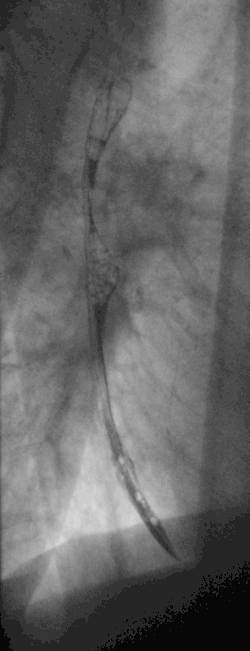

Masa esofágica media -